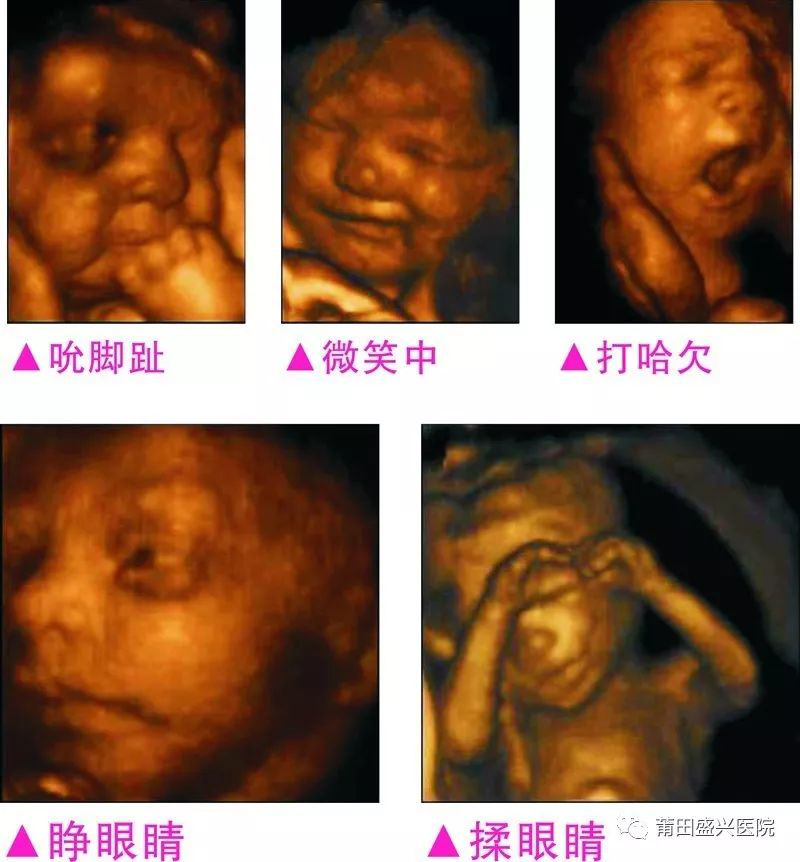

您一定不知道寶寶有多調(diào)皮可愛

你一定不知道寶寶這么小就有這么多表情

3完整記錄胎兒高清動態(tài)寫真

四維容積成像技術(shù),智能光源系統(tǒng)展現(xiàn)梯度亮度,渲染畫面,提高容積成像品質(zhì),高清顯示腹中寶寶的實時動態(tài)影像,完整記錄寶寶的一舉一動,讓準爸媽與寶寶Di一次幸福“見面”,更可刻錄成高清視頻,送給未來寶寶的珍貴禮物。